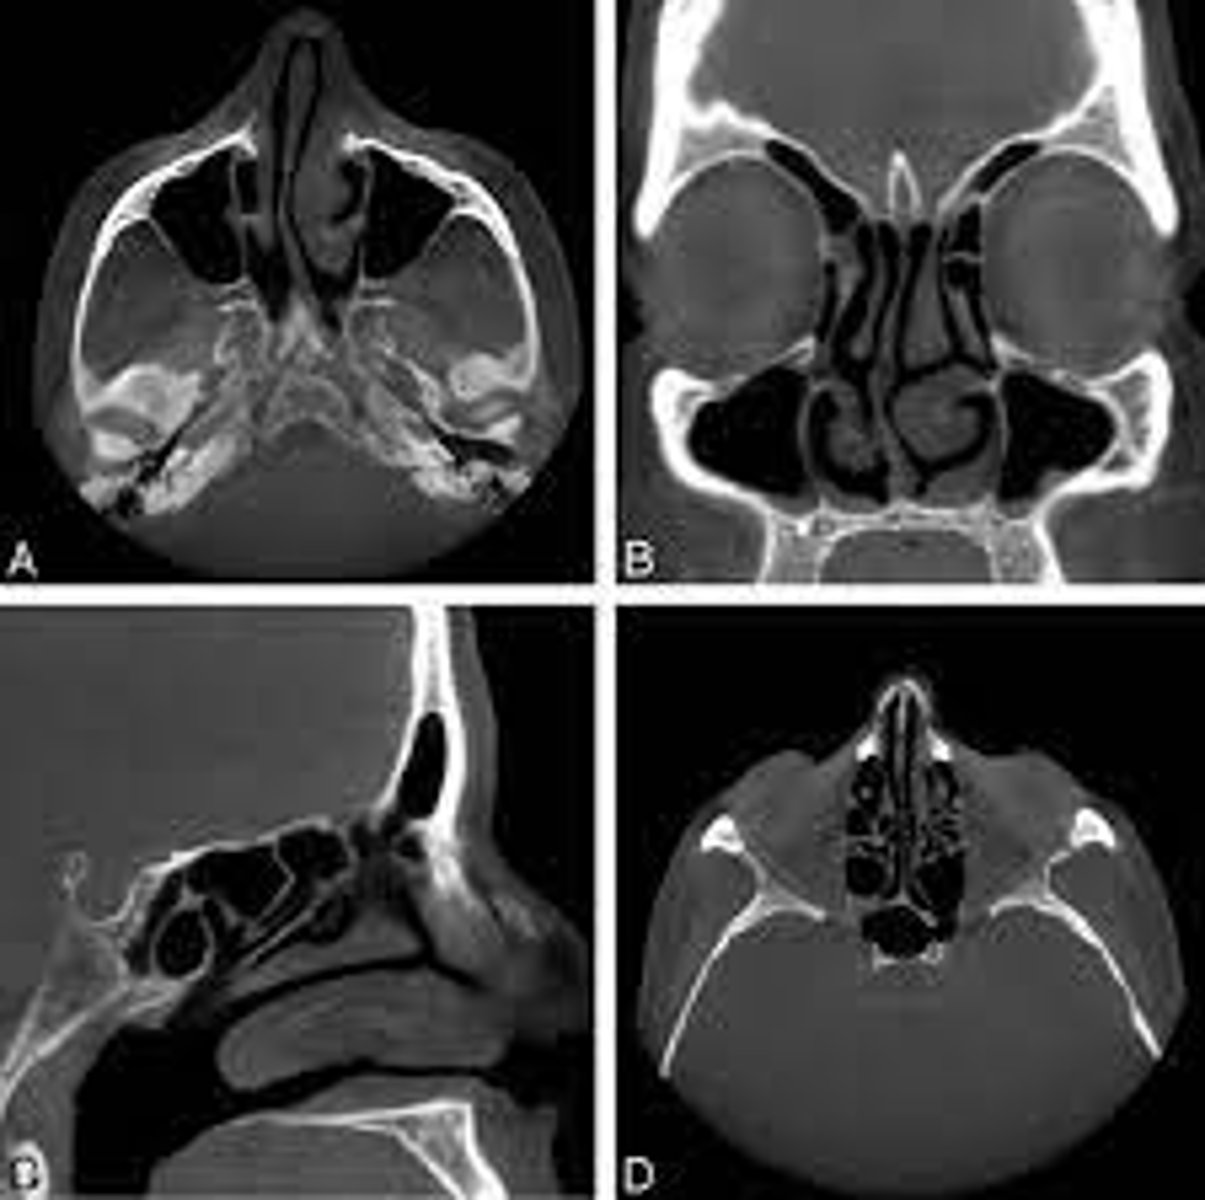

CBCT

ID the type of Imaging modality:

- Pano

- CT

- CBCT

- MRI

- Technetium 99 bone scans

- PET